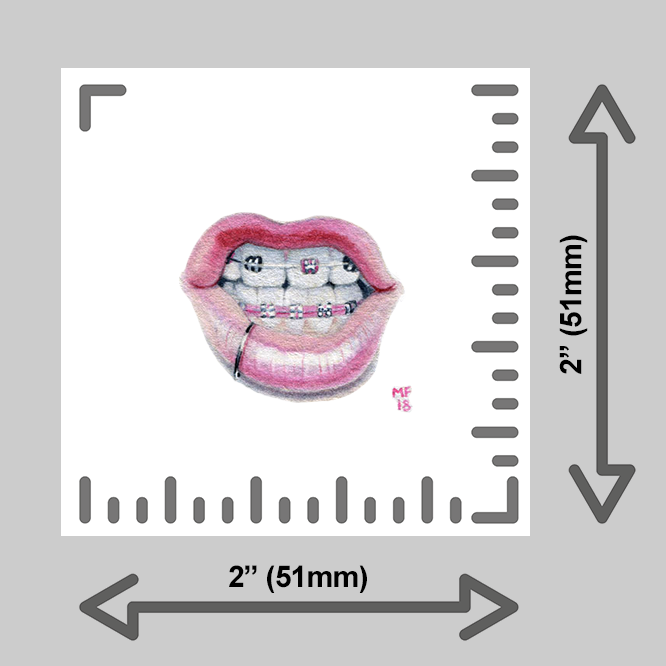

learn more about these prints below:

Each tiny print is made by hand by yours truly in my Michigan studio using an EPSON P600 printer. Only the finest heavy matte archival, museum-quality, paper is used; color and finish are inspected thoroughly for each print before framing and shipping.

Want to upgrade your print? Add a wee frame! You have four options for framing your tiny print:

A sturdy 2×2” wood frame with a saw tooth hanger, or,

A 2×2” clear acrylic magnet frame, or,